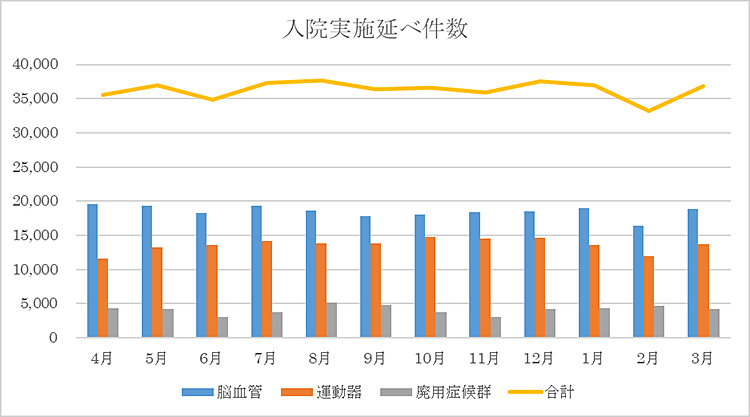

リハビリテーション科の実績

【平成30年度 リハビリ実施入院延べ患者数】